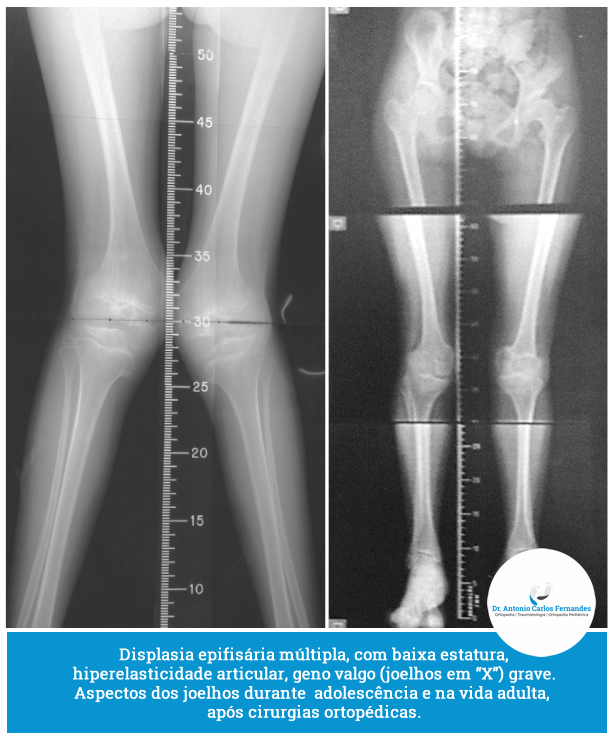

Para o diagnóstico são considerados os aspectos clínicos, radiográficos e exames genéticos. O diagnóstico é muitas vêzes difícil, devido às alterações e o acometimento de vários órgãos e sistemas do organismo.

O exame clínico detalhado fornece inúmeros subsídios para o diagnóstico, assim como para a proposta de tratamento. Os itens mais relevantes são descritos. A altura é geralmente menor, em muitas displasias. A forma e o aspecto da face, tronco e membros podem auxiliar no diagnóstico. Alterações da pele, unhas e pelos também podem contribuir para o diagnóstico.

Deve ser individualizado para cada criança e seguir as características da doença. O tratamento inicial deve estimular as etapas motoras, que geralmente encontram-se atrasadas. O tratamento ortopédico deve seguir a correção das deformidades, tendo como princípios minimizar o tempo de imobilizacão, permitindo movimento precoce .